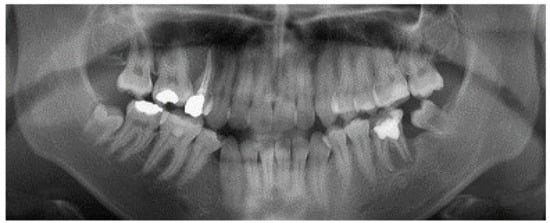

2. Case Report